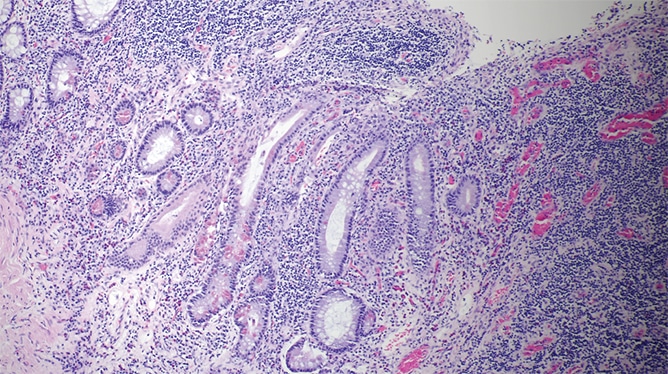

The resection specimen contained suppurative granulomatous appendicitis and active chronic enterocolitis (Figs. 1–3). Granulomatous inflammation was also noted in the endoscopic biopsies of the right colon (Fig. 4), explained Dr. Zenali, assistant professor of pathology, Department of Pathology and Laboratory Medicine, UConn Health.

Yersiniosis often involves the terminal ileum/ileocecal region and mesenteric lymph nodes; it may also affect the appendix. Suppurative and granulomatous patterns are common in Yersinia enterocolitica and in particular in Yersinia pseudotuberculosis, Dr. Zenali said. “Patients can have concurrent mesenteric lymphadenitis. The organism accesses the bowel wall through the microfold [M] cells of the Peyer’s patches, so the inflammatory reaction often initiates from the terminal ileum and ileocecal valve and can further spread to the right colon.”